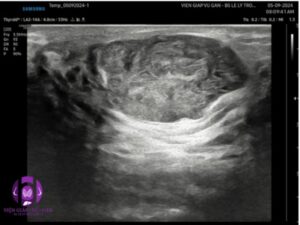

SIÊU ÂM ( (máy Samsung V8) ghi nhận:

VÚ PHẢI:

- Vị trí ¼ trên ngoài 2 có cấu trúc hình bầu dục, echo kém tương đối đồng nhất, giới hạn rõ, bờ đều, trục ngang, không vôi kt # 44 x 30 x 20 mm và 30x20x10mm . Doppler: mạch máu phân bố ít. Siêu âm doppler vi mạch vài dòng mạch máu thưa thớt ở ngoại vi và trung tâm.

- Hạch nách chưa ghi nhận hạch bệnh lý.

- Kết luận: ĐA TỔN THƯƠNG VÚ PHẢI BI-RADS 3 NGHĨ BƯỚU SỢI TUYẾN